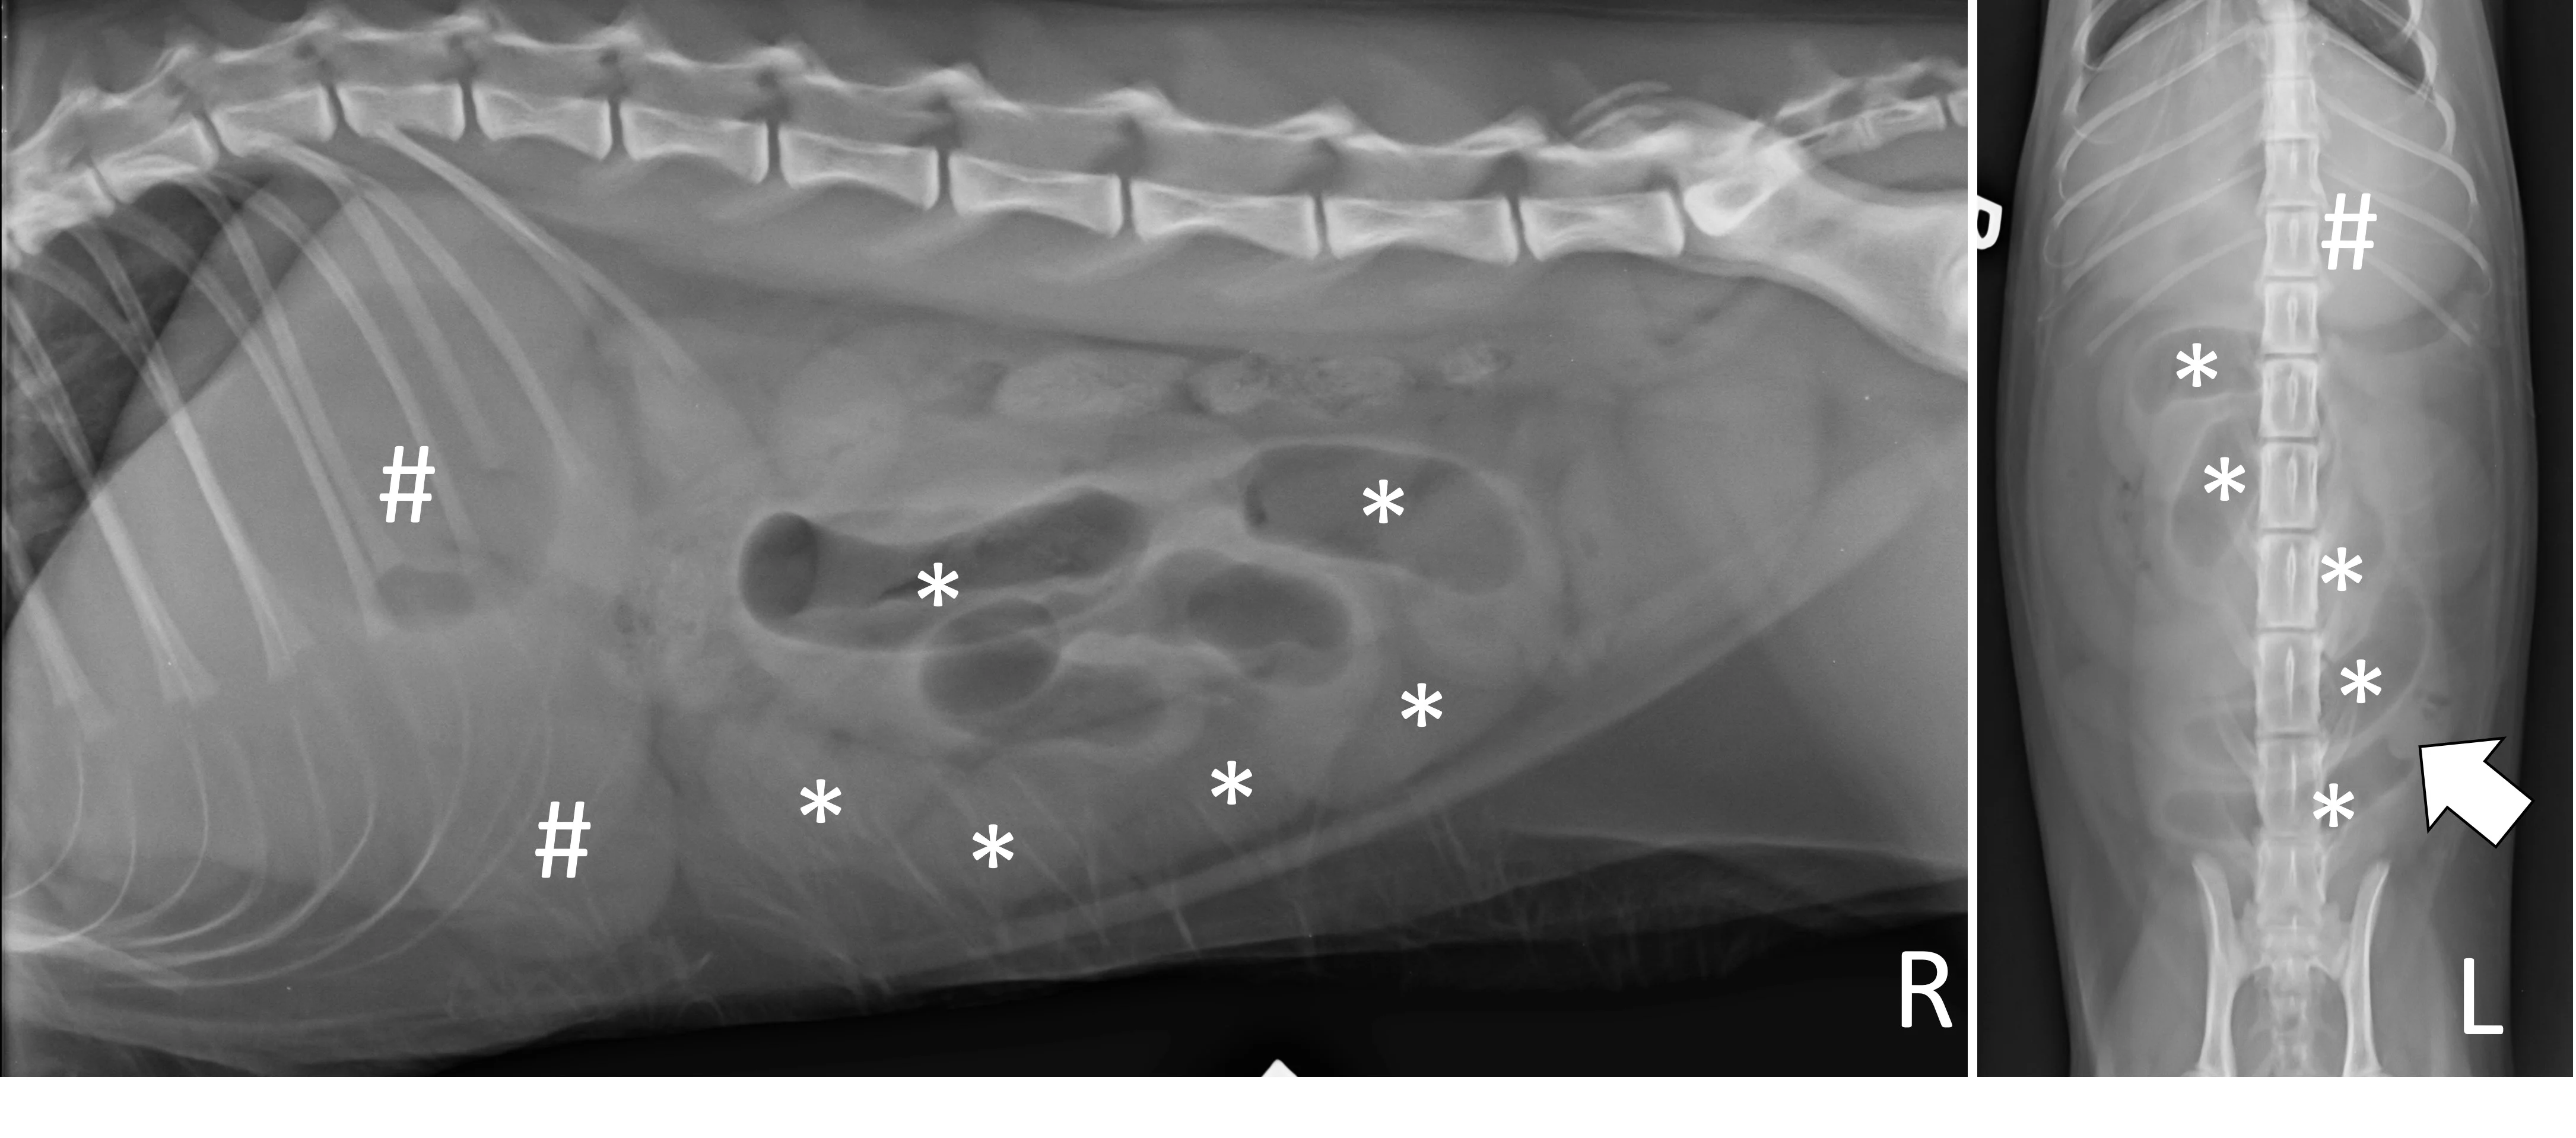

A complete radiographic study includes left lateral, ventrodorsal, and right lateral projections. Obtaining a left lateral projection and performing projections in the aforementioned order can improve visualization of the pylorus and duodenum by shifting gas into the lumens.3 Normal intraluminal gas is an in vivo negative contrast agent that can make soft tissue opaque foreign bodies (eg, cloth) easier to see (Figure 1).

Three-view abdominal radiographs of a 6-year-old spayed dachshund with an acute pyloric outflow obstruction secondary to a surgically confirmed foreign body (cloth). The stomach (pound signs) is moderately dilated with gas and fluid. On the left lateral and ventrodorsal projections, gas outlines an irregularly shaped soft tissue opaque foreign body (arrows) within the pylorus that extends into the duodenum. On the right lateral projection, the foreign body is more difficult to see because it is surrounded by similarly opaque gastric fluid.